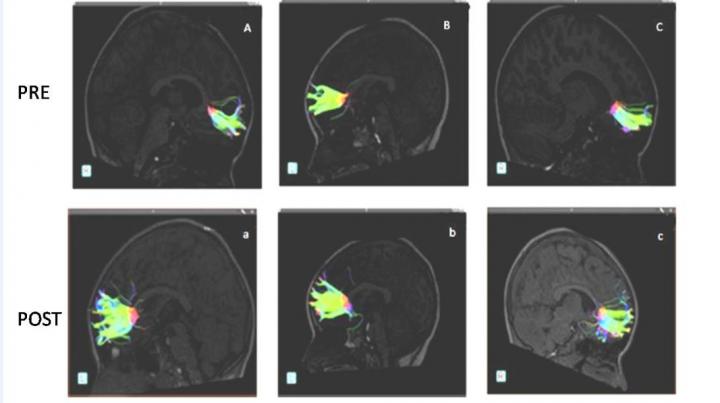

The study participants underwent pre- and post-musical-training evaluation with diffusion tensor imaging (DTI) of the brain. DTI is an advanced MRI technique, which identifies microstructural changes in the brain’s white matter.

[Fibers belonging to the greater forceps prior to musical training are observed (A, B, C). Fibers belonging to the same patients after 9 months of musical training are observed below]

After the children in the study completed nine months of musical instruction using Boomwhackers–percussion tubes cut to the exact length to create pitches in a diatonic scale, DTI results showed an increase in FA and axon fiber length in different areas of the brain, most notably in the minor forceps.